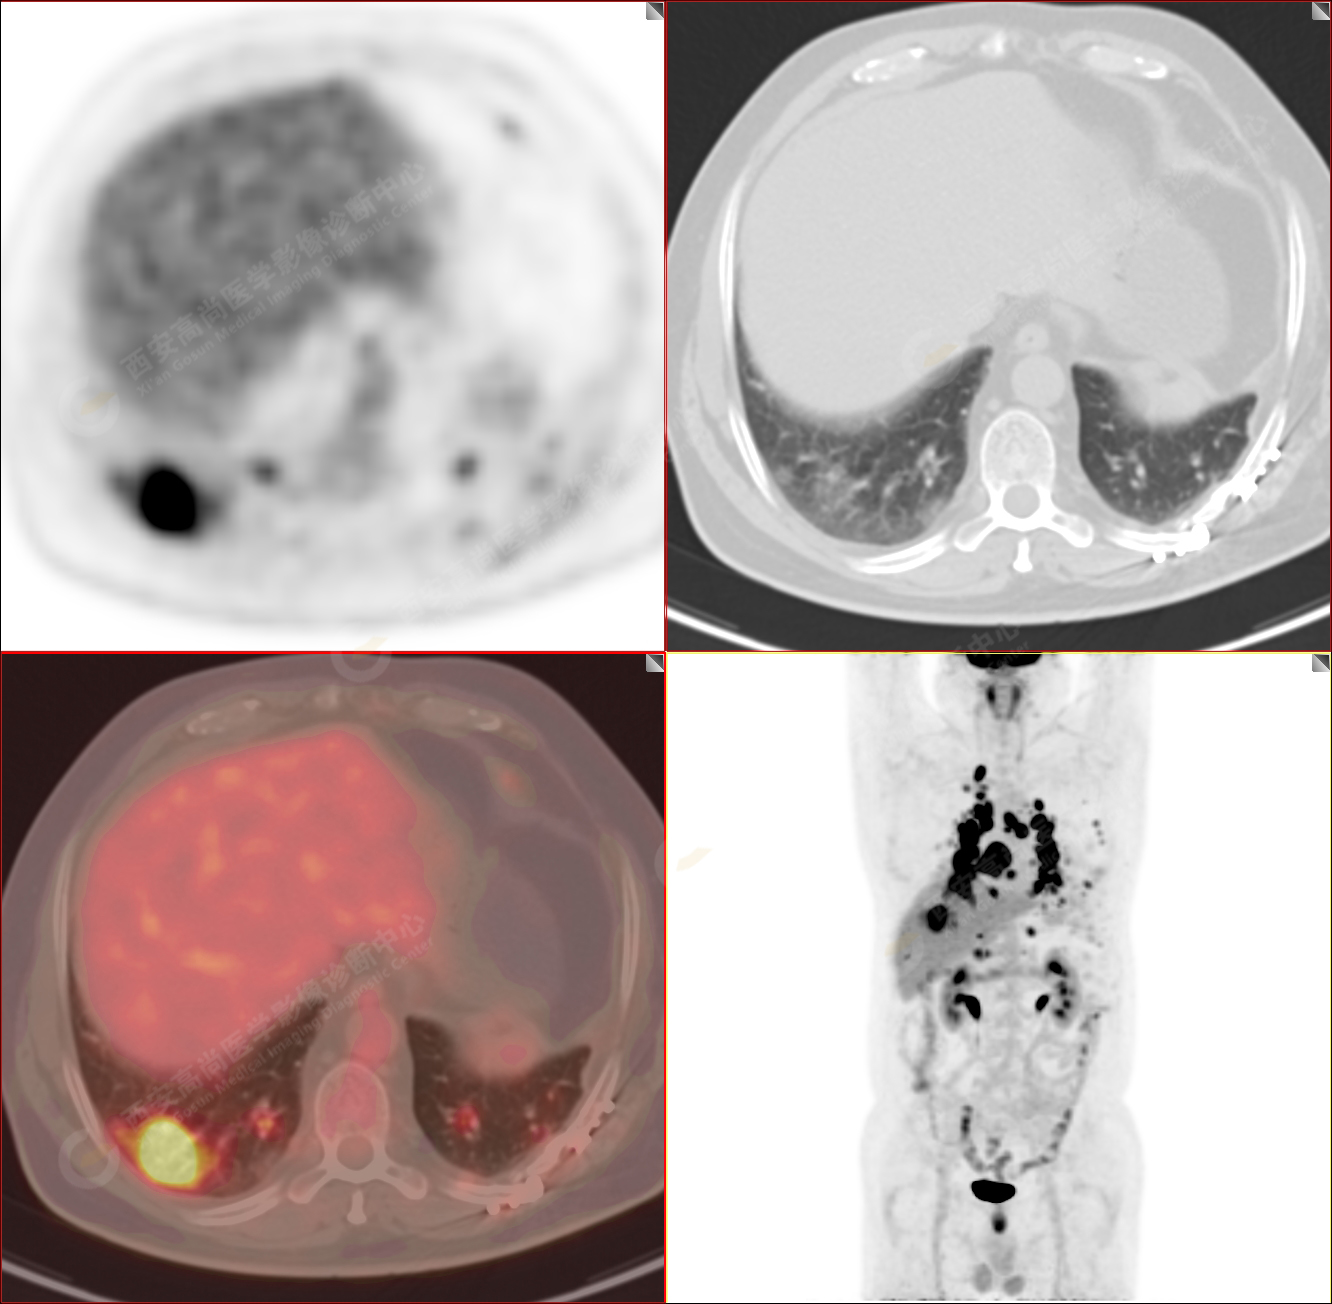

PET/CT-MR診斷結(jié)節(jié)病雙肺及全身多發(fā)淋巴結(jié)廣泛累及1例【西安高尚病例】

男性,53歲,頭暈半月入院,CT發(fā)現(xiàn)肺內(nèi)腫塊,雙肺多發(fā)大小不等實(shí)性及粟粒樣結(jié)節(jié),雙肺門(mén)及縱隔多發(fā)腫大淋巴結(jié)。病程中無(wú)發(fā)熱、胸悶氣及胸部不適。既往:左側(cè)肋骨外傷史。

PET-MR圖像